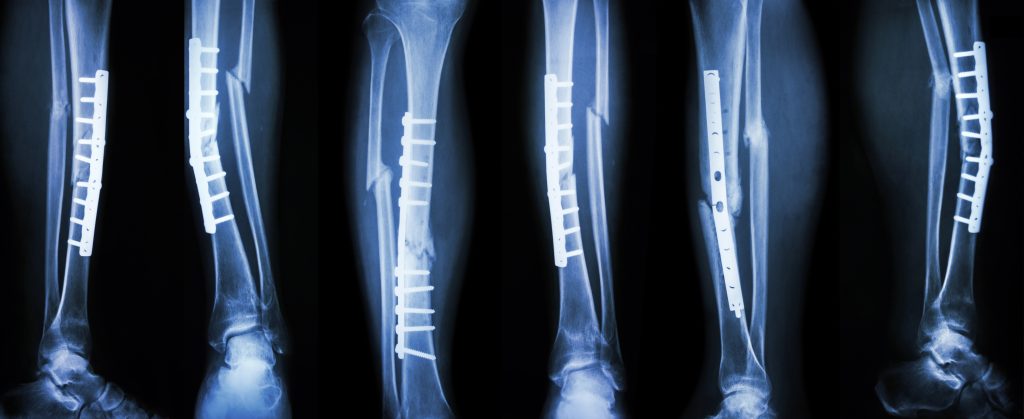

Накістковий остеосинтез:

Використовується для фіксації уламків кісток за допомогою спеціальних пластин, які прикріплюються до поверхні кістки за допомогою гвинтів.

Сучасні кутові стабільні пластини забезпечують надійну фіксацію навіть у випадках складних переломів та остеопорозу.